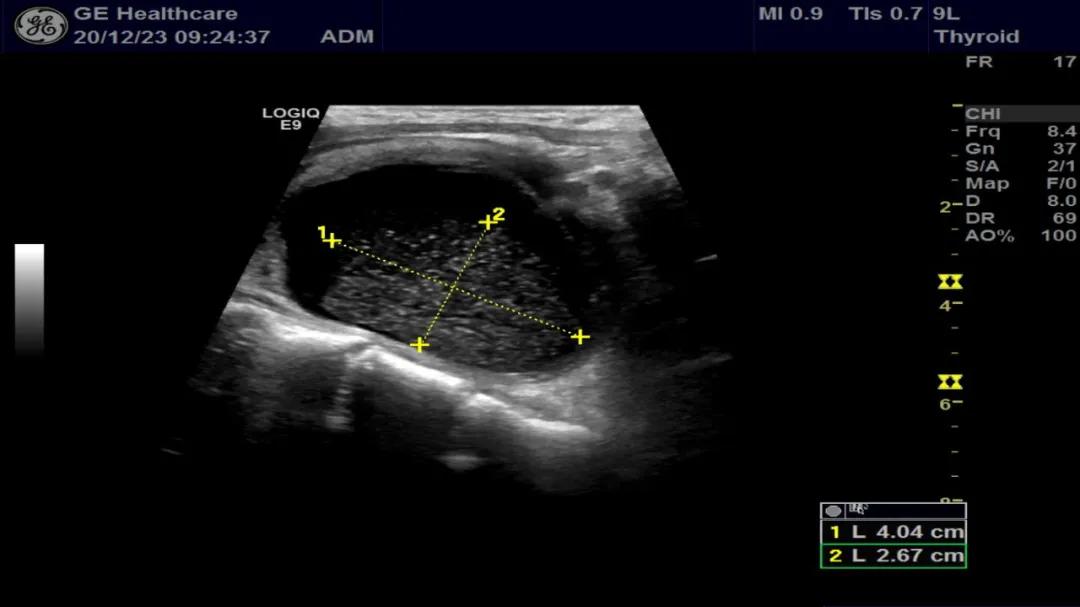

李先生经常规超声检查发现,甲状腺左叶可见两个囊性回声,大小分别约4.5×3.1cm和5.3×3.6cm,内见点絮样中等回声。为进一步确认囊性包块内是否有实性成分,医生为李先生做了遂行超声造影检查,发现均无造影剂填充,其内絮样回声考虑为囊肿内积血。